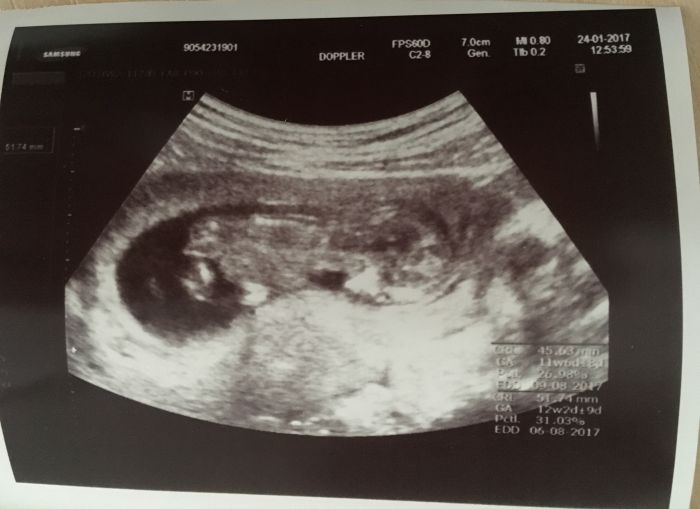

Holky tak jsem zpet z kontroly ;-) vse je v poradku mimisek ma 4cm a je uzasnyy ;-) hematom se vstrebal, dostala jsem prukazku a 7.2 jdu na screening. Takze za me super. Dokonce mi dr. Rekla ze podle srdecnich ozev tipuje kluka, tak jsem fakt zvedava ;-) Slonice to jsou dobre zpravy ja bych na ten odber taky sla, udelala jsi dobre a zjisti ti z toho i pohlavi miminka?

Anicko krasnej mimisek ;-) tak gratuluji k dobrym zpravickam ;-)

krásná fotka skvělý zprávy

Anicko, krasna fotka :-).

Jinak ja taky po kontrole a miminko je v poradku (bylo naherne ho videt), ale ten hematom tam porad je (+boli me dnes pekne bricho), takze pristi tyden na dalsi kontrolni ultrazvuk a kdyz bude dobry, tak uz odbery krve a zacne se testovat. Jsme od vas trochu opozdena, kdyz mam termin cca 26.8.2017